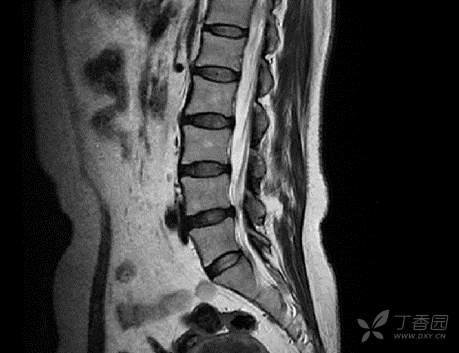

2. 腰椎核磁:腰骶椎退变,L2-3、L4-5椎间盘略膨出。